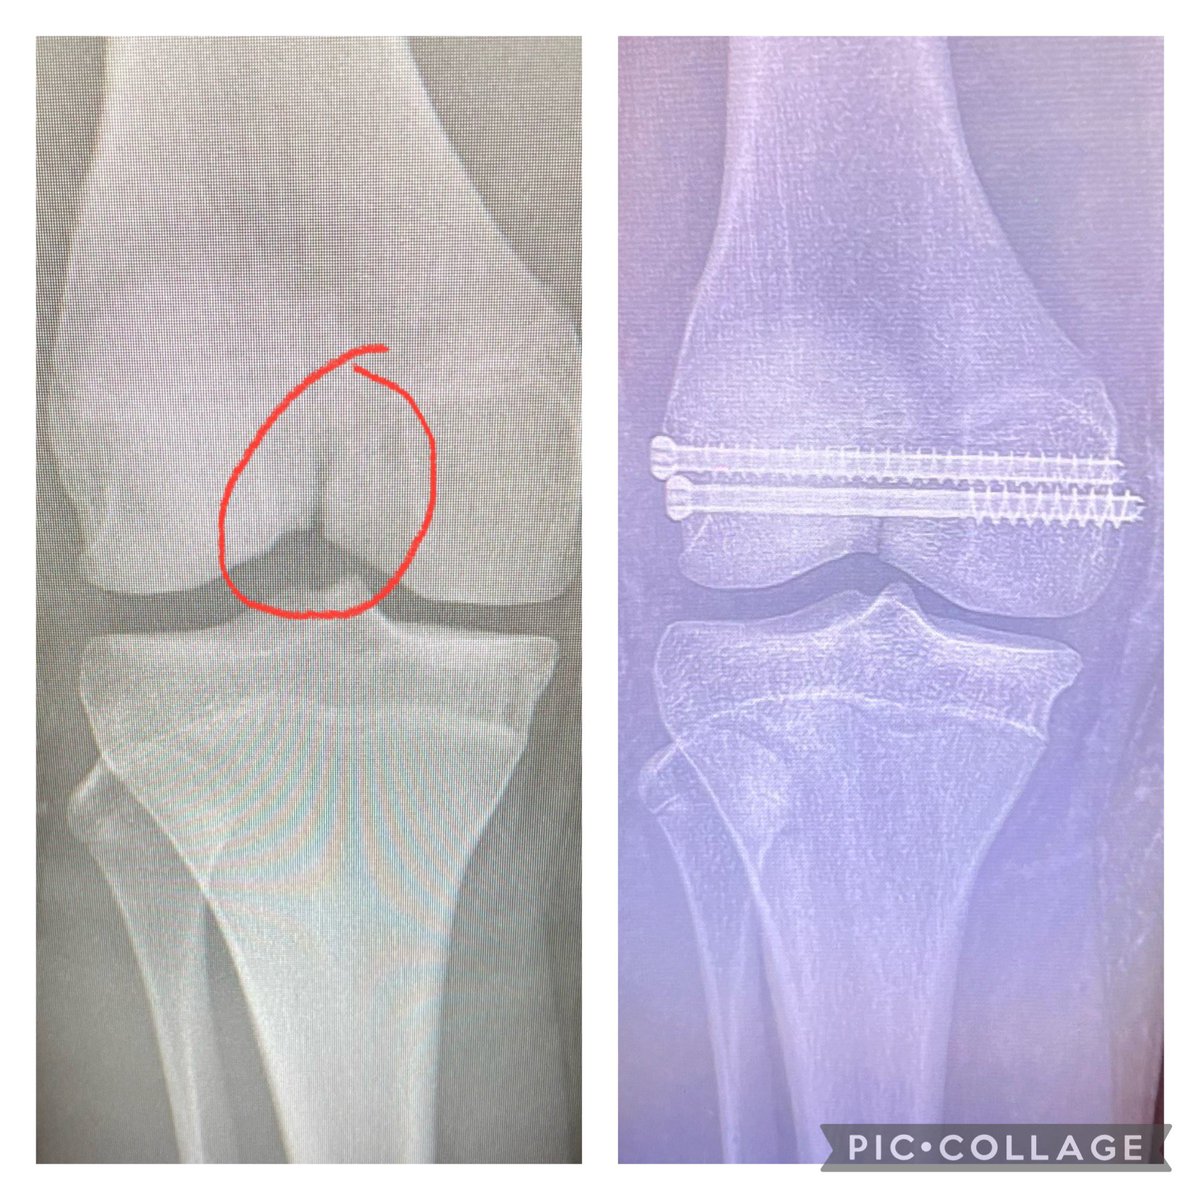

Although he was on pace for much more before his fractured femur; here, as you can see, he is pleased with 510 - 20 weeks post operation.

Sophomore Season Highlights (7.5 games due to fractured femur) Full released and working on Junior year now. Check out below. 55 TT 35 Solo 6 TFL 6 QB hurries 2 Sacks 2 Forced fumbles 3 Fumble recoveries https://t.co/lYsHFOuMlu